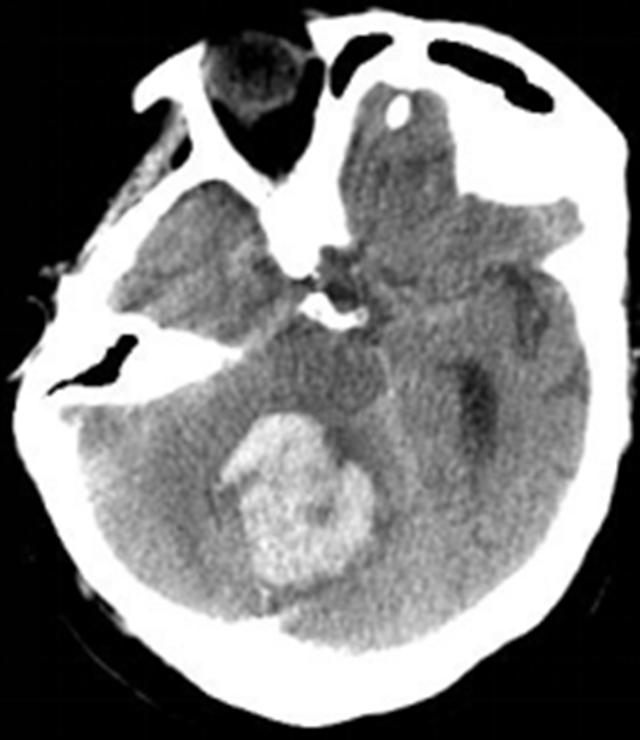

脑出血是神经外科常见的急症之一,当脑出血发生后,最关键的就是要及时鉴别并且进行相应的处理措施。越早进行干预患者的预后就会越好,脑出血症状表现有哪些?

对于脑出血的症状形式,要根据本身脑出血的严重程度来进行分析,如果比较严重,发病比较急,容易引起颅内压明显升高,从而会表现为剧烈的头痛,伴随呕吐,甚至出现意识障碍。

如果只是轻微的脑出血,主要会产生有头痛、头晕,以及口角歪斜的情况,可以通过头部影像学的方法来进行检查确诊。在病情没有继续发展的前提下,要注意监测和控制血压,防止后期出现有病情复发的现象。

出现上述症状时应立即前往医院行头颅CT、CTA等检查,排除是否有脑出血的发生。

基底节区

小脑

脑干